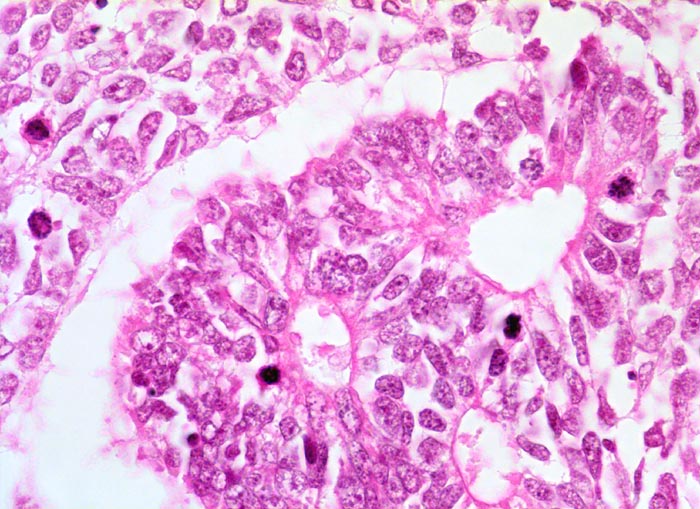

Tubuli ausgekleidet von stark basophilem Epithel mit grossen Kernen. Kerne mit kleinen Nukleolen und grobem Chromatin. Daneben solide Blastemkomponente mit ähnlicher Zytomorphologie. In beiden Komponenten finden sich Mitosen.

Graubrauner scharf begrenzter weicher Tumor mit fokalen Nekrosen und Einblutungen.